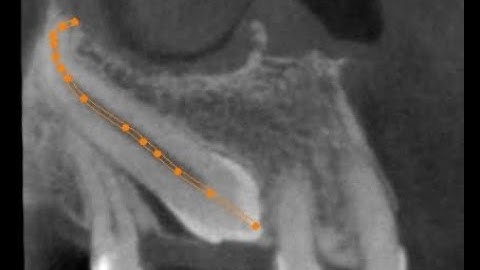

Auto-Transplantation of 28 to Replace 27 - Dr Nyer Firdoose C S